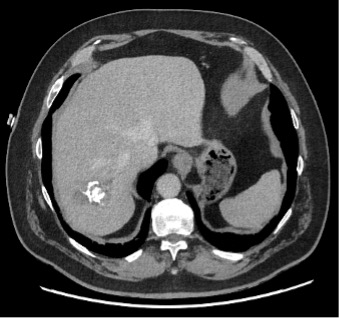

Ce CT-scanner, initialement réalisé chez une patiente de 70 ans à la recherche d’une dissection aortique scanner, met fortuitement en évidence une lésion hépatique.

Les douleurs de la patiente ont bien évolué sous traitement symptomatique. Son bilan sanguin avec FSS, CRP, tests hépatiques et pancréatique est dans la norme. Au vu de la présence de lésions kystiques hépatiques présentant des calcifications et des zones de nécrose sur le scanner, une sérologie pour l’échinococcose alvéolaire (EA) est demandée.

Le diagnostic de la maladie se base sur l’imagerie et la sérologie. L’US hépatique ainsi que le CT-scanner ou l’IRM peuvent être utilisés, mais les deux derniers permettent d’évaluer l’extension de la maladie. En cas de lésions calcifiées, le PET/CT au FDG permet de déterminer le degré d’activité métabolique de la lésion.